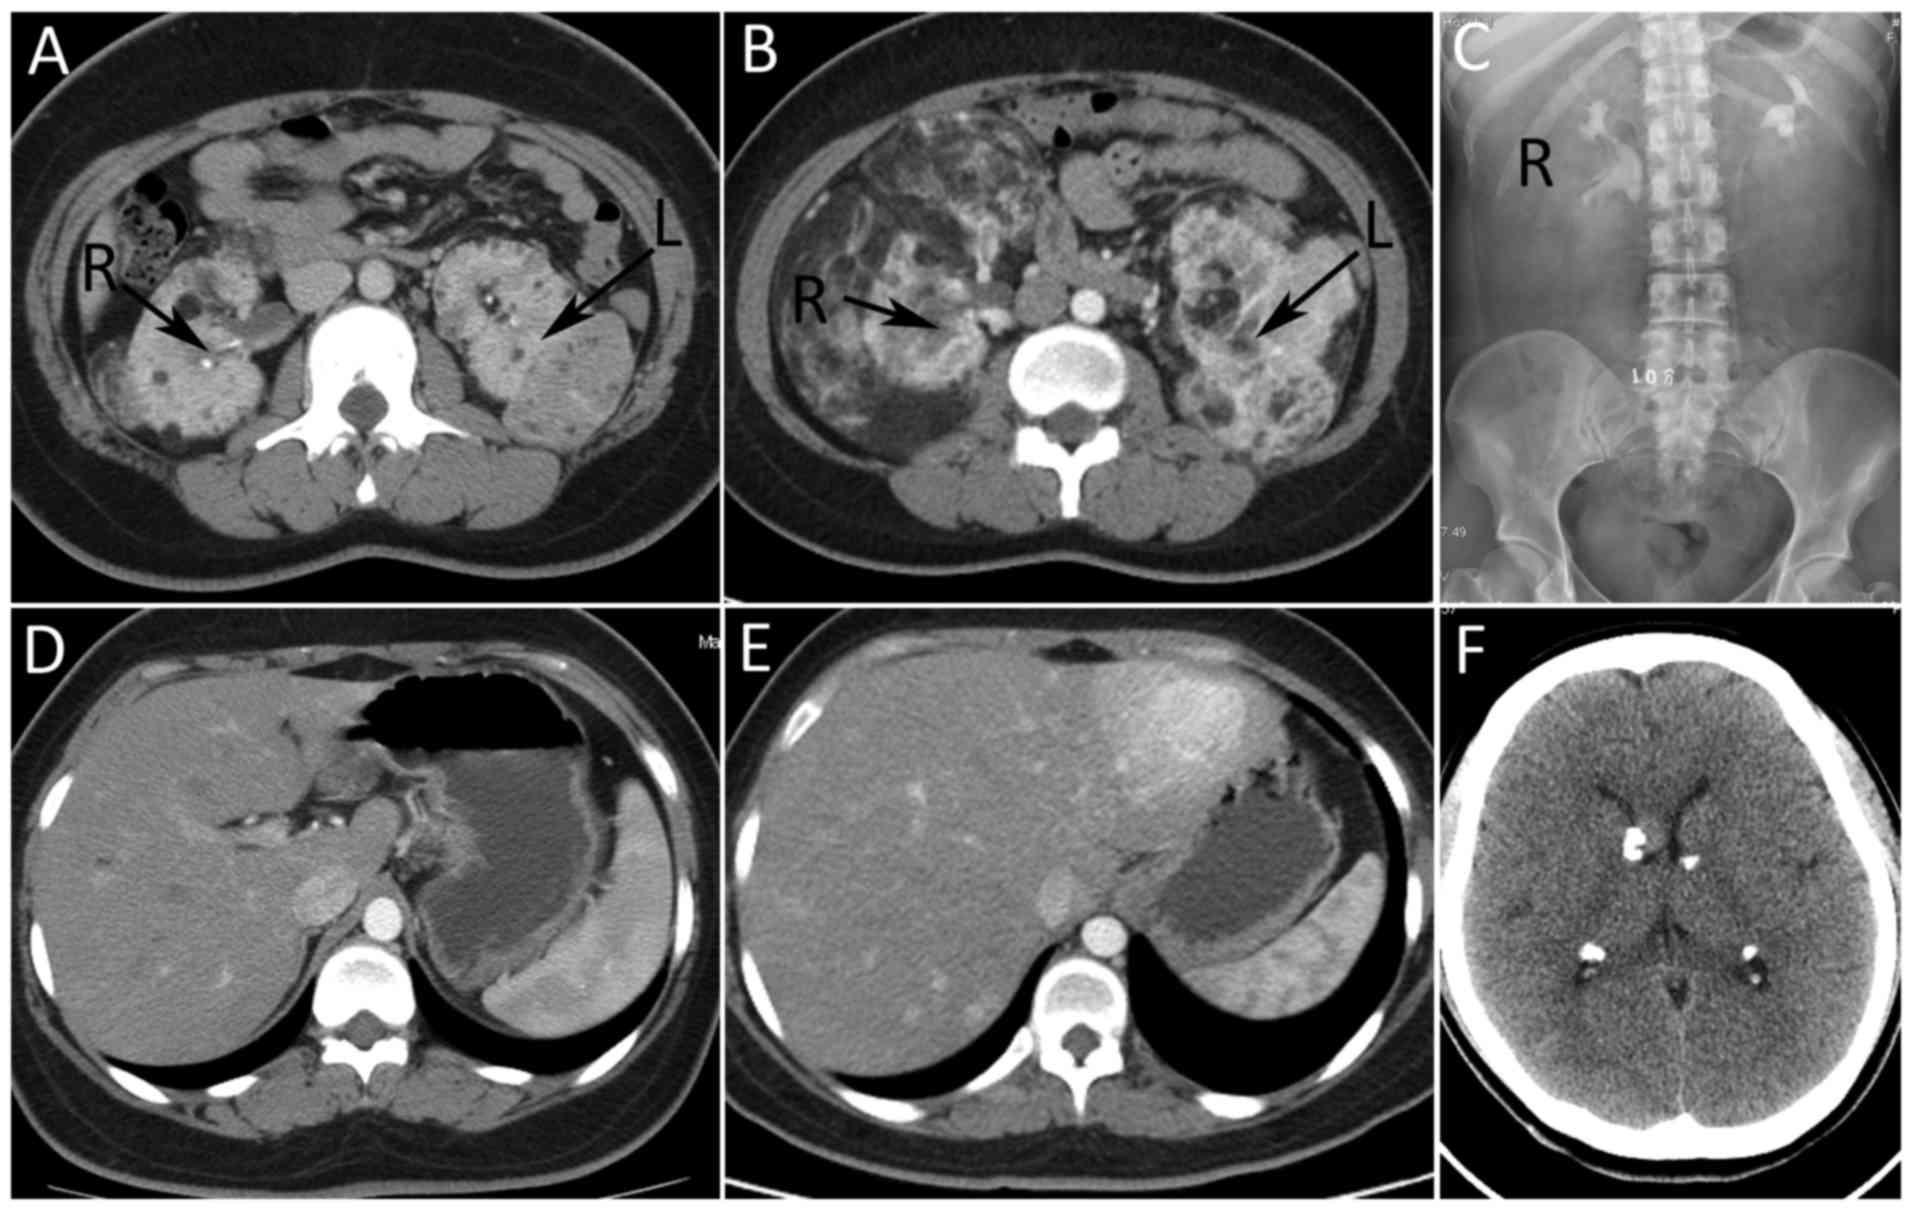

Familial genetic tuberous sclerosis complex associated with bilateral giant renal angiomyolipoma: A case report

Tuberous sclerosis complex (TSC) is an autosomal dominant disease involving multiple organs, but there are a limited number of reports on family TSC. In the present report, a case of a 52‑year‑old female with a familial genetic TSC, associated with bilateral giant renal angiomyolipoma, was described. The mother, second elder brother and daughter of the patient all exhibited TSC, but the clinical manifestations, and therapeutic prognosis between the family members were not the same. The present case report aimed at identifying an effective diagnostic method and treatment through additional study of familial genetic TSC, in order to prolong and improve the quality of life for patients with TSC. According to the present case and relevant literature reviews, it is suggested that fetal gene detection during pregnancy could prevent the passing of this disease onto further generations. Furthermore, early application of drug treatment may control the development of the disease in diagnosed patients. The combination of classical treatments with a small dose of mammalian target of rapamycin inhibitors is the typical recommendation, which may control the development of the disease more effectively and decrease adverse side‑effects.